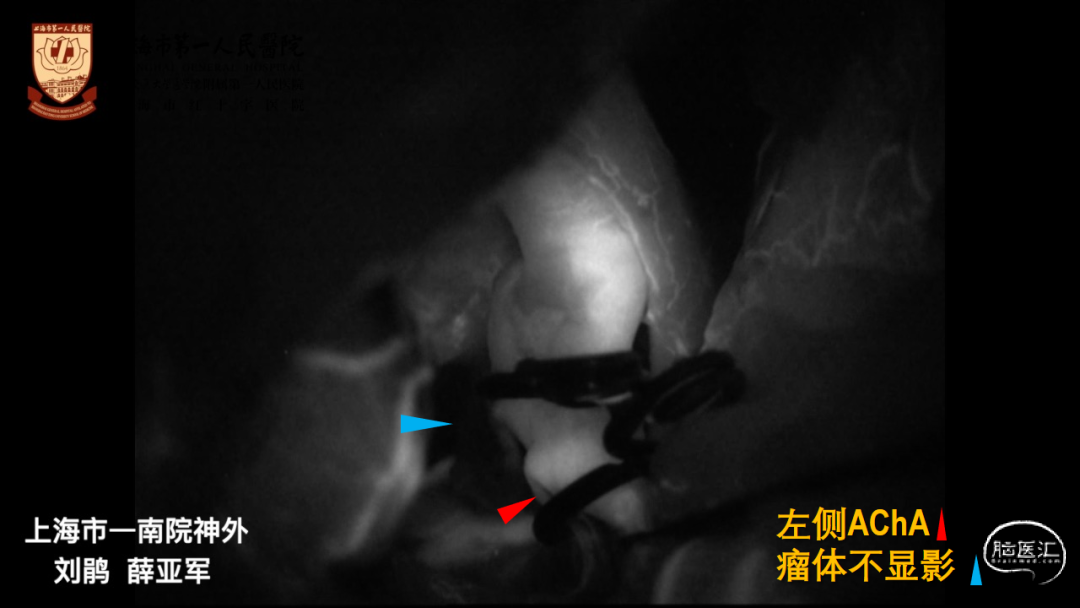

CTA:左侧大型后交通动脉瘤,指向后、外、下

胚胎型后交通动脉,必须保留

夹闭术有利于彻底夹闭瘤体,保留后交通动脉

窗式夹利弊:

窗式夹可用于后壁宽颈动脉瘤

窗式夹释放较困难,不利于保护ICA后、内侧壁发出的穿支